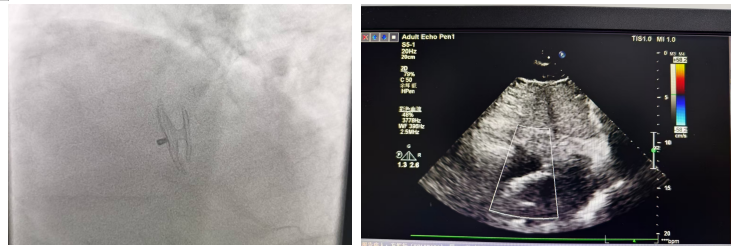

针对方先生的病情,吕安林院长团队经过反复研讨,制定了“经皮卵圆孔未闭封堵术”的微创治疗方案。然而,手术的难度远超预期:方先生年事已高,心脏结构存在严重转位,这给术中定位带来了极大挑战,同时也导致封堵器释放时张力显著增高,任何一个操作失误都可能引发严重并发症。面对这一高难度手术,吕安林院长凭借三十余年的心血管介入经验,沉着应对、精准操作。术中,他通过DSA血管造影系统实时引导,小心翼翼地将封堵器送至卵圆孔未闭处,在最佳位置成功释放,精准封堵了缺损。同时,为了减少患者二次手术的痛苦和经济负担,吕院长团队还在同一次手术中为方先生完成了冠脉造影检查,全面评估了心脏血管情况。整个手术过程流畅顺利,仅用较短时间便圆满完成。